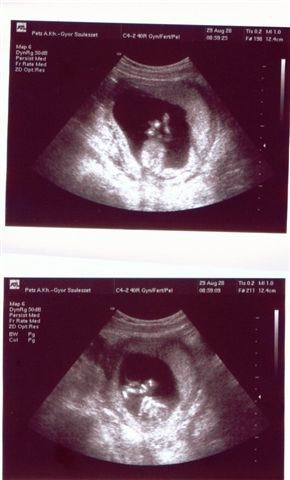

Egyelőre még reménykedünk, mert egy dolog, hogy babát várunk, de szeretnénk biztosak lenni benne, hogy egészséges, rendben van, hiszen 40 felett, első babával minden előfordulhat.